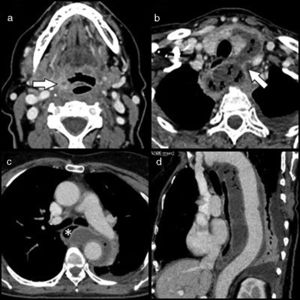

En el estudio realizado se identifica un pequeño absceso en el seno de la amígdala palatina derecha (fig. 1a) que comunica con el espacio visceral infrahioideo ipsilateral a través de un trayecto fistuloso descendente que atraviesa el espacio parafaríngeo. A continuación, se forma una colección que sigue una ruta pretraqueal, atravesando la línea media en el plano graso subyacente a la capa superficial de la fascia cervical profunda, para posteriormente seguir un recorrido peritiroideo y retroceder introduciéndose en el tórax a través del orificio torácico superior izquierdo (fig. 1b). A su entrada alcanza sus máximas dimensiones asociando burbujas de gas, y se dispone de forma tubular en el mediastino medio y posterior rodeando casi por completo a la aorta torácica descendente en toda su longitud hasta su transición tóraco-abdominal (figs. 1c y d).

a) Corte axial de la TC cervical a nivel de la epiglotis, observándose un absceso milimétrico en la porción inferior de la amígdala palatina derecha (flecha); b) Corte axial de la TC cervical a nivel del tiroides, identificándose una colección con gas que rodea el lóbulo tiroideo izquierdo anteriormente, para después progresar posteriormente introduciéndose en el tórax a través del orificio torácico superior izquierdo (flecha); c) Corte axial de la TC torácica a nivel de la carina, se visualiza la colección situada en mediastino medio y posterior rodeando a la aorta torácica en más de 180°. Ejerce efecto de masa sobre el esófago medio (asterisco), y d) Corte sagital oblicuo de la TC torácica donde se aprecia la colección extendiéndose a lo largo de toda la longitud de la aorta torácica descendente. Se aprecia derrame pleural de pequeña cuantía.